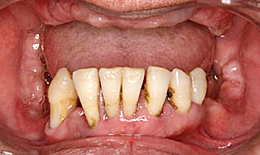

インプラント症例(25)50歳 男性

治療前

下顎

インプラントを7本埋め込んで、セラミックスクラウンを被せた